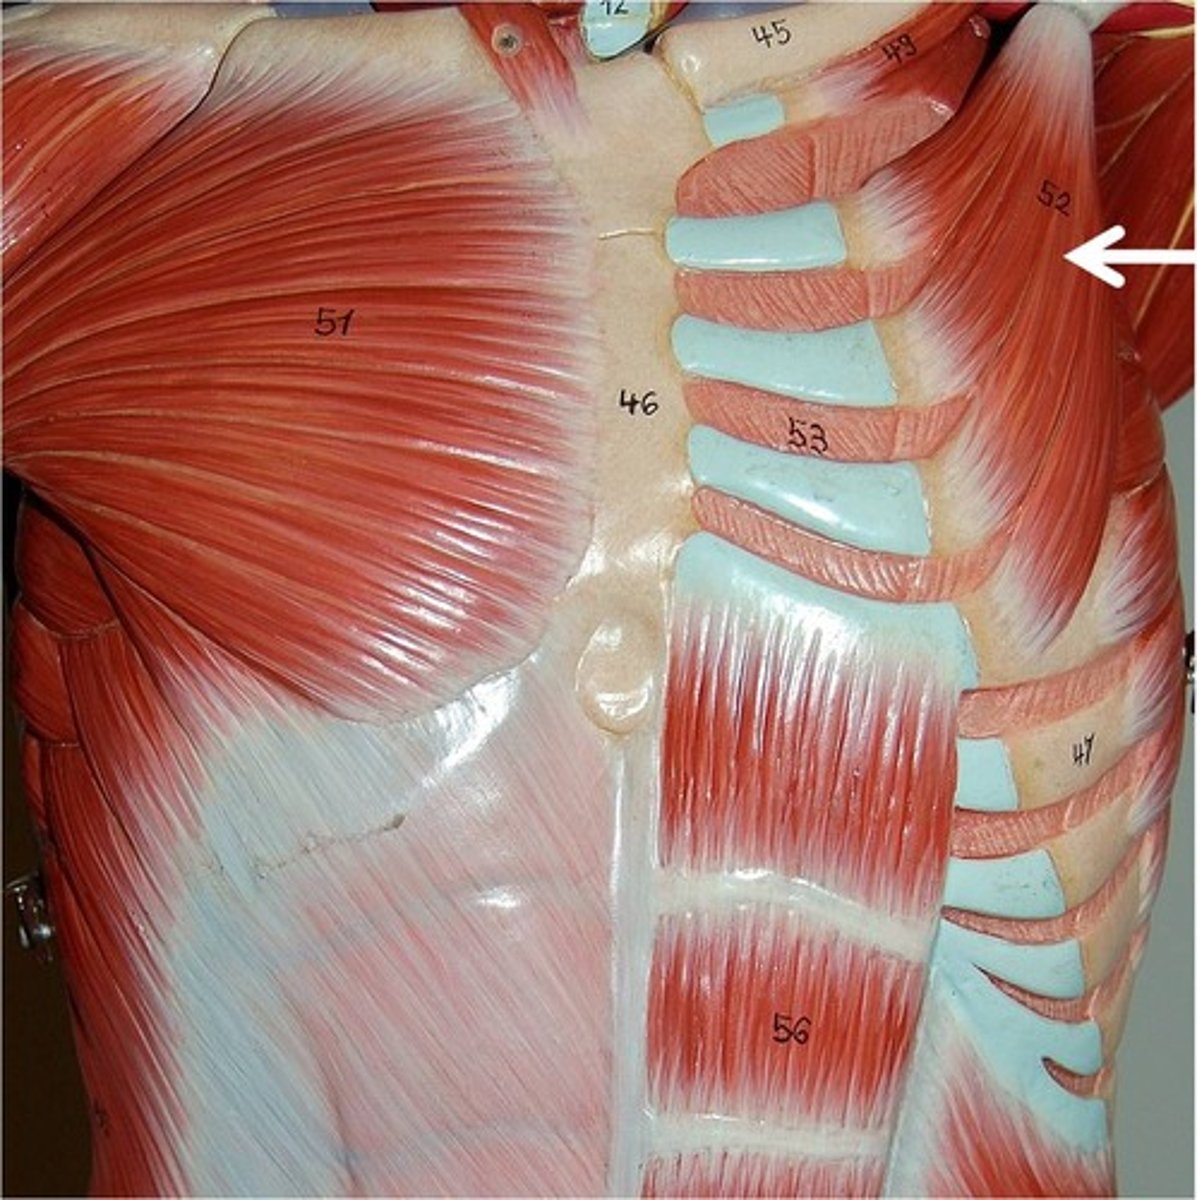

Rhomboid Major

Rhomboid Minor

Just the top "line"

Trapezius

Latissimus Dorsi

Pectoralis Major

Pectoralis Minor

Serratus Anterior

Subclavius

Levator Scapulae